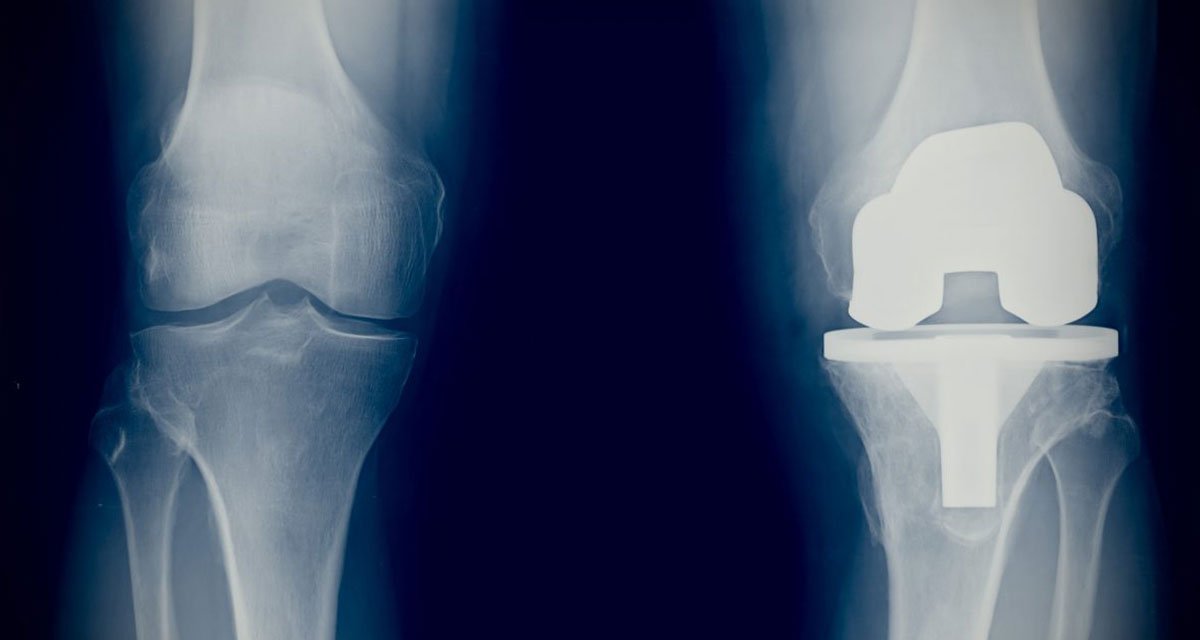

Revision Joint Replacement Surgery

Revision Joint Replacement Surgery & Periprosthetic Fracture Management Also Managed Expertly At Our Hospital. Complex cases such as revision joint replacement surgeries and periprosthetic fracture management are also handled with a high level of expertise at our hospital. These procedures require advanced surgical skills and careful planning, which are provided by our experienced orthopedic team. By using modern techniques and individualized treatment protocols, we ensure optimal outcomes even in challenging scenarios, helping patients recover safely and regain functional mobility. Our hospital provides the comprehensive support and surgical expertise needed to restore mobility, reduce pain & improve your quality of life.